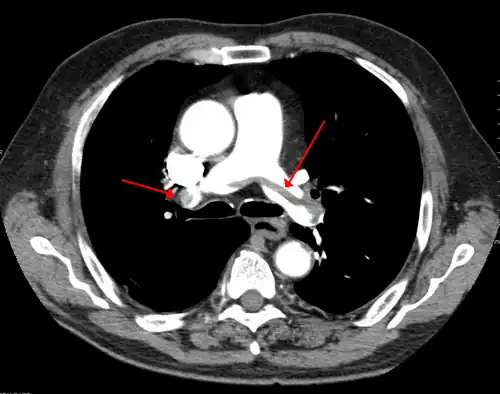

A pulmonary embolism (PE) occurs when a blood clot from a deep vein (a DVT) detaches from a vein (embolizes), travels through the right side of the heart, and becomes lodged as an embolus in a pulmonary artery that supplies deoxygenated blood to the lungs for oxygenation.[28] Up to one-fourth of PE cases are thought to result in sudden death.[12] When not fatal, PE can cause symptoms such as sudden onset shortness of breath or chest pain, coughing up blood (hemoptysis), and fainting (syncope).[29][30] The chest pain can be pleuritic (worsened by deep breaths)[29] and can vary based upon where the embolus is lodged in the lungs. An estimated 30–50% of those with PE have detectable DVT by compression ultrasound.[30]

A rare and massive DVT that causes significant obstruction and discoloration (including cyanosis) is phlegmasia cerulea dolens.[31][32] It is life-threatening, limb-threatening, and carries a risk of venous gangrene.[33] Phlegmasia cerulea dolens can occur in the arm but more commonly affects the leg.[34][35] If found in the setting of acute compartment syndrome, an urgent fasciotomy is warranted to protect the limb.[36] Superior vena cava syndrome is a rare complication of arm DVT.[11]

DVT is thought to be able to cause a stroke in the presence of a heart defect. This is called a paradoxical embolism because the clot abnormally travels from the pulmonary circuit to the systemic circuit while inside the heart. The defect of a patent foramen ovale is thought to allow clots to travel through the interatrial septum from the right atrium into the left atrium.[37][38]